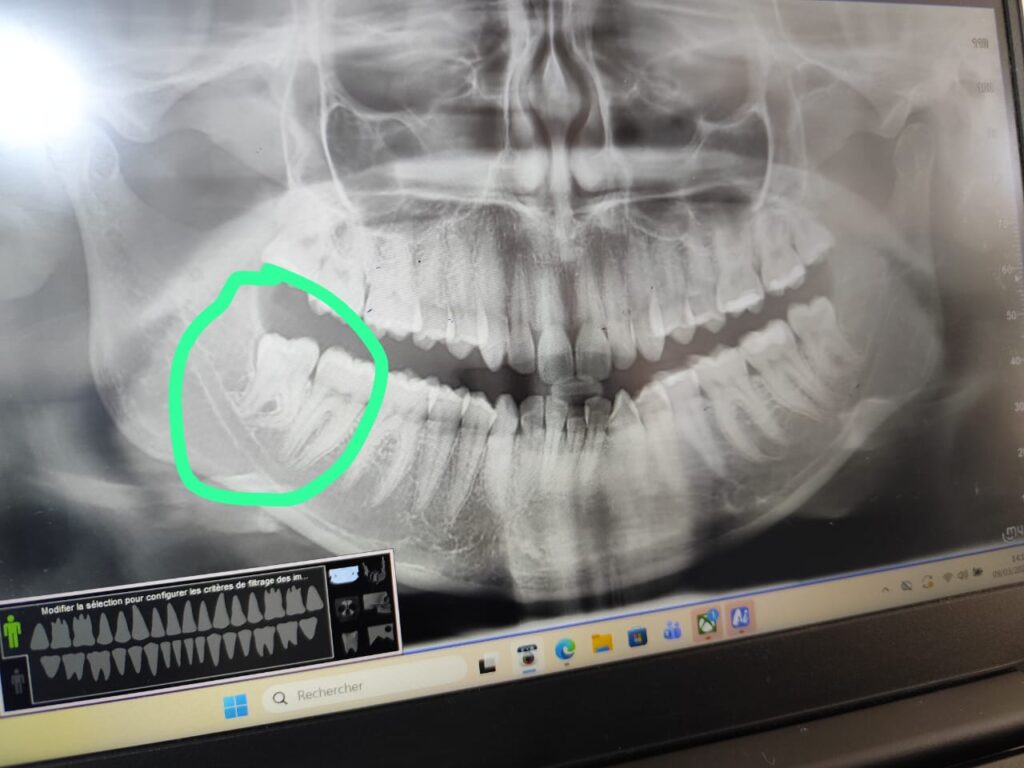

EL BARNOUSSI CHAIMAE – Tangier – Extraction